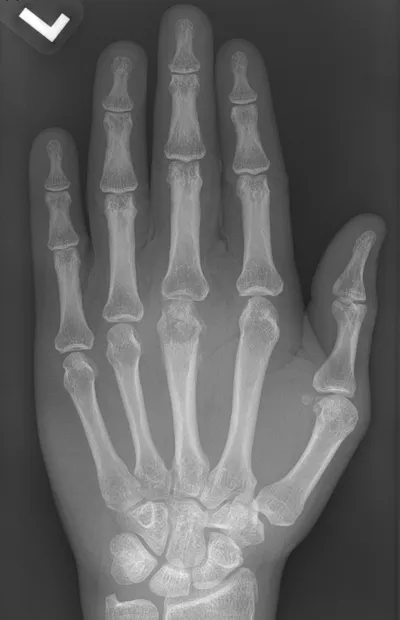

This collection contains 1 radiology images related to sequestrum, including various imaging modalities such as X-rays, MRIs, CT scans, and ultrasound images commonly used in medical diagnosis and education.